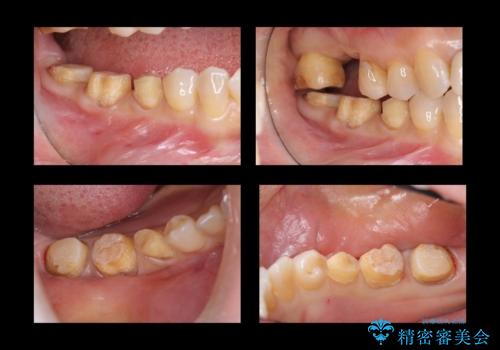

奥歯の高さがない 歯周外科で解決

- 右下奥歯(7番)の高さがなく、かぶせ物(クラウン)にするためにあらかじめ歯周外科手術を行いました。(クラウンレングスニング)

右下5番は歯ぐき付近までWSD(くさび状欠損)で削れていたため、患者様と相談してクラウンにしました。その際、削れていたのが歯肉縁下に及んでいたため、一緒に手術範囲に含めました。

- 56.1万円(右下567 ジルコニアクラウン11万円×3 歯周外科手術APF 15万円 仮歯1万円×3)費用は治療当時の料金となります

歯の高さを出すとかぶせ物(クラウン)がはずれにくくなります。